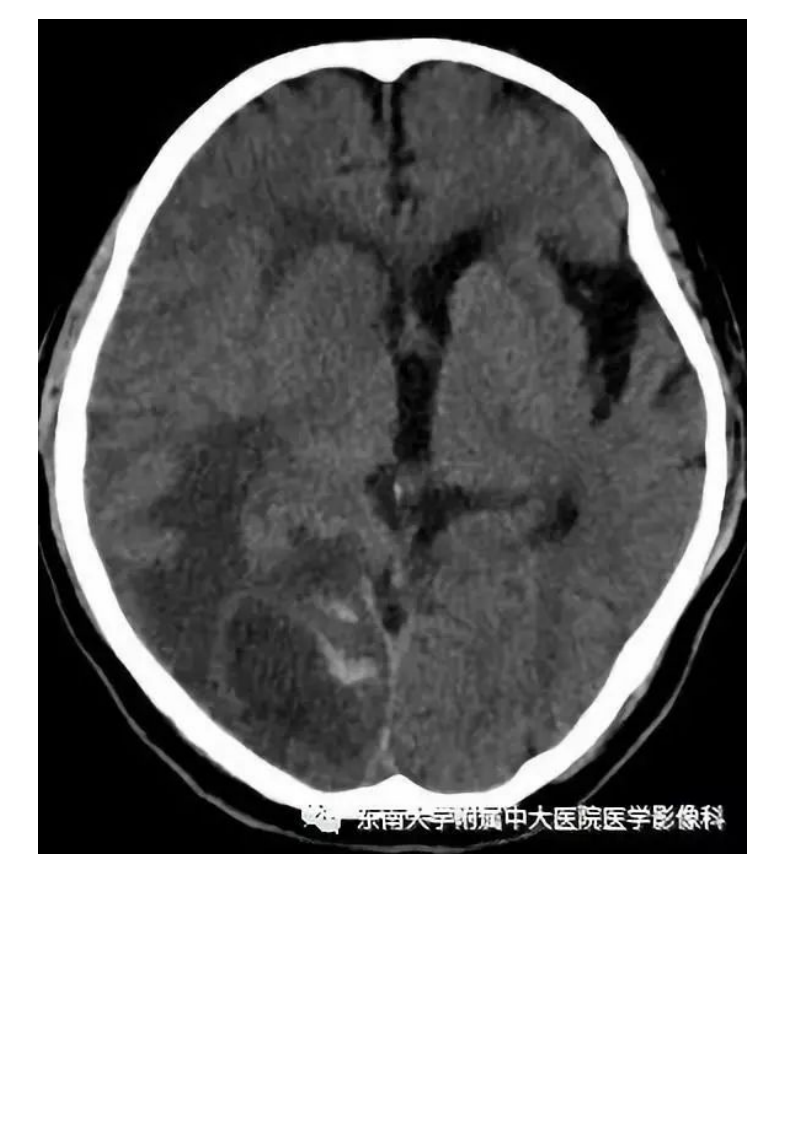

20190909_2【晨读结果公布】2019.09.09神经系统疾病.pdf